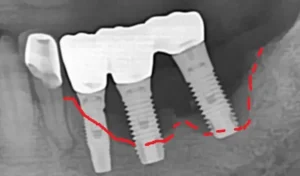

In our previous posts, we discussed various factors influencing dental implant failure. In this post, we will specifically focus on patient-related factors that can affect dental implant failure. (1) Poor Bone Quality and Quantity Many individuals lose their teeth due to periodontitis (gum disease). While some seek gum treatment to save their natural teeth upon … Continue reading Patient Factors Affecting Dental Implant Failure